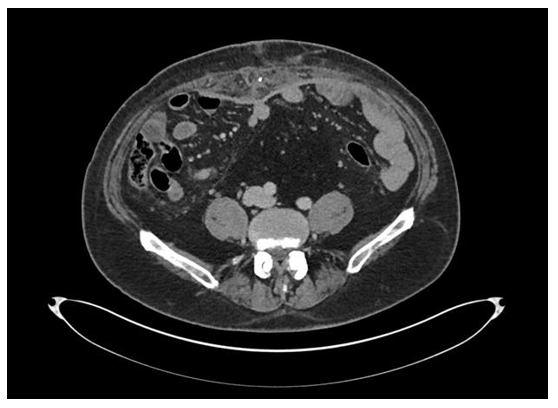

A postoperative CT-scan obtained 4 weeks postoperatively showed satisfactory repair of the hernia with re-approximation of the rectus abdominis muscles in the midline and an underlay of Extra Thick Strattice acellular dermal matrix (Figure 4). A postoperative Ovio 360 degree photo analysis demonstrated an excellent result with anatomical repair of the hernia defect and no evidence of redundant skin in either the vertical or horizontal dimensions (Figure 5) (Video 2).

Figure 4 Post-operative CT scan obtained at approximately 4 weeks postoperatively demonstrated anatomic repair of the hernia with excellent approximation of the rectus abdominis muscles in the midline. The Strattice acellular dermal matrix could be seen in the underlay position and with great apposition against the abdominal wall.